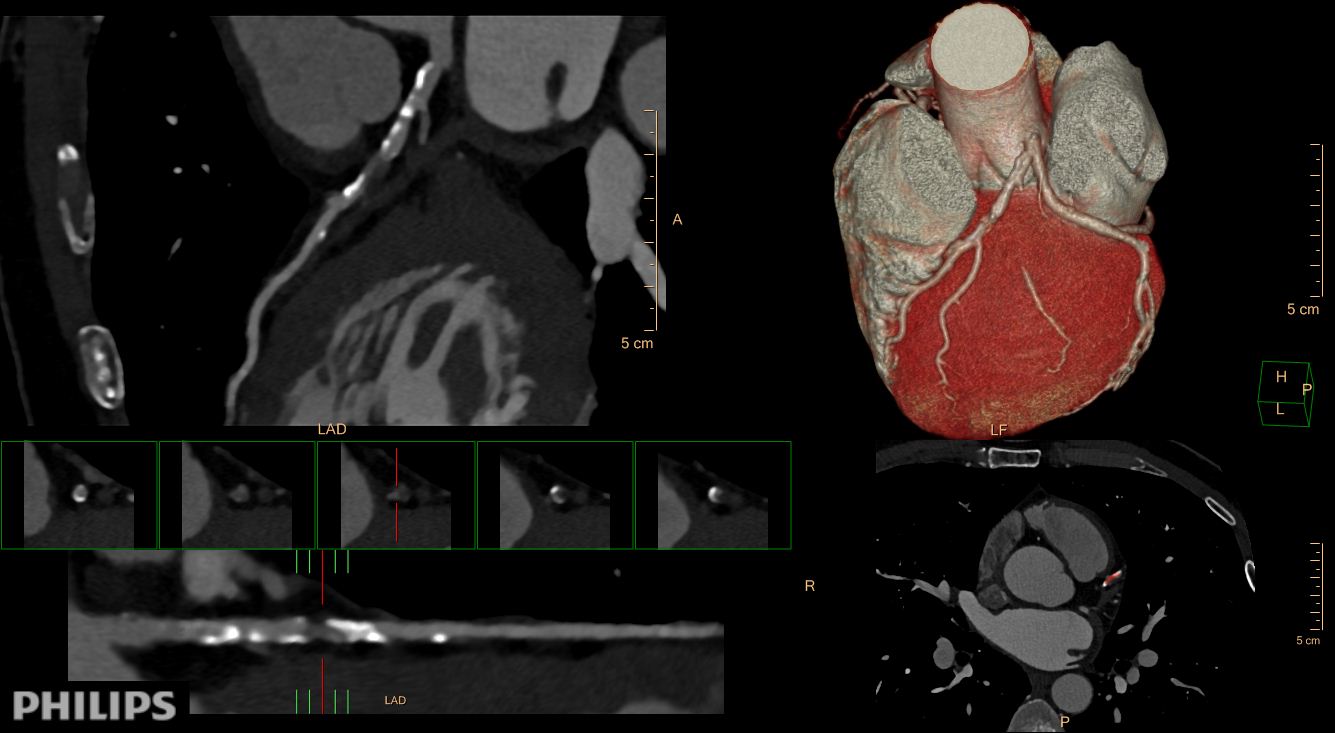

Multi-Society Group Releases CAD-RADS for Standardized Coronary CT Angiography Reporting

CT-Guided Therapeutic Decision-Making Enables Reduction in Myocardial Infarction